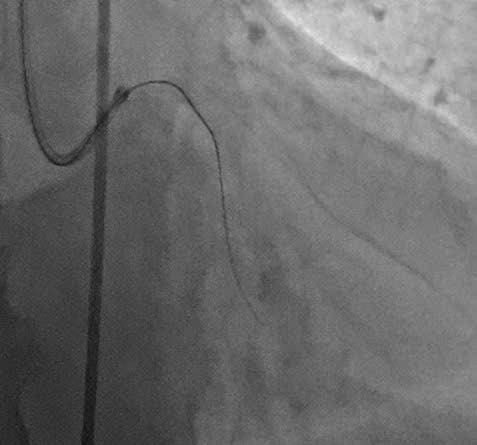

Đưa dây dẫn siêu cứng qua tổn thương động mạch mũ - Ảnh BVCC

Dưới sự dẫn đường của hệ thống chụp mạch xóa nền kỹ thuật số (DSA), đội ngũ bác sĩ đã phối hợp chặt chẽ, sử dụng các dụng cụ chuyên biệt gồm dây dẫn siêu nhỏ và siêu cứng (guidewire) với sự hỗ trợ của các vi ống thông (microcatheter) để tiếp cận và đưa dây dẫn qua vị trí tắc mạn tính của động mạch vành mũ. Sau đó, các bác sĩ đã đặt 01 Stent tái thông động mạch mũ một cách an toàn.

Kết quả, nhánh động mạch mũ tắc hoàn toàn mạn tính đã được tái thông hoàn toàn, phục hồi dòng máu nuôi dưỡng cơ tim, chấm dứt các triệu chứng thiếu máu cơ tim và mở ra cơ hội sống cho người bệnh.

Sau can thiệp, bệnh nhân hết đau ngực, không khó thở, các chỉ số sinh tồn ổn định và được xuất viện chỉ sau 4 ngày điều trị.